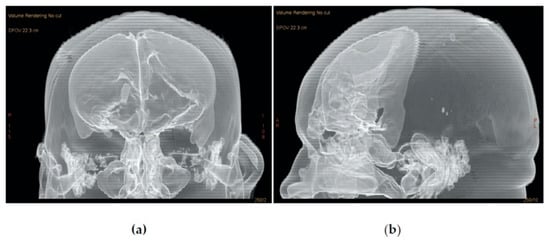

2.2. Surgical Approach and Reconstruction Technique